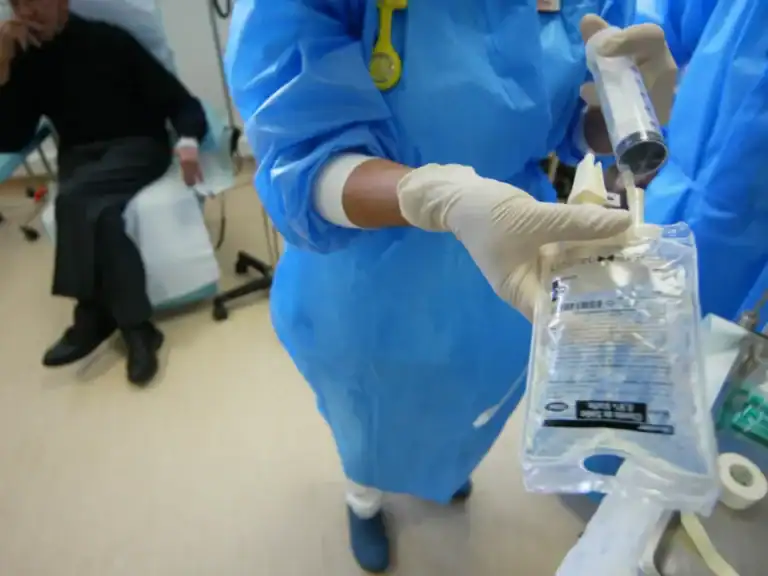

Portugal transplantou o maior número de órgãos de sempre em 2023

Portugal registou em 2023 cerca de mil transplantes de órgãos.

Mais de 1.600 enfermeiros saíram de Portugal em 2023

Cerca dos 60% inscritos este ano.